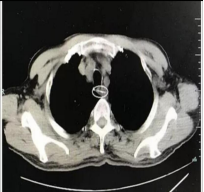

鱼刺等异物容易卡在食管入口处和其他两处食管狭窄处,可造成这些部位的组织感染,如果异物穿透食管,可引起颈部和纵隔感染,危及呼吸,从而危及生命。异物残留引起这些严重的并发症时,不但会增加取异物的难度,而且在异物取出后,继发性大出血和术后感染风险也会明显增加。